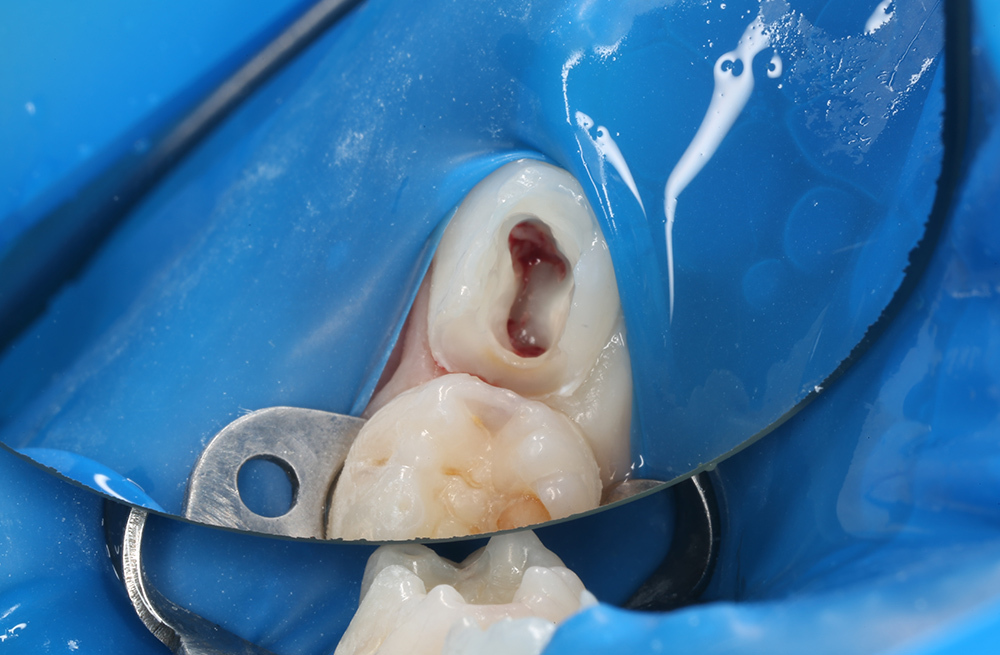

Защита ослабленного молочного зуба металлической коронкой после эндодонтического лечения

Лечение осложнённого кариеса молочного зуба в условиях ЗАКС и протезирование коронкой

Как мы вылечили пульпит и сохранили молочный зуб у ребёнка 5 лет

Как мы сохранили молочный зуб коронкой после лечения сложного пульпита у ребёнка под ЗАКС

Детское лечение пульпита без боли с сохранением зуба

Восстановление зуба коронкой после лечения пульпита

Восстановление молочного зуба с помощью коронки при пульпите

Лечение хронического пульпита с установкой коронки на зуб ребенку